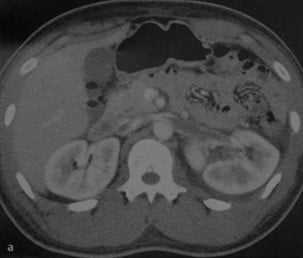

(Слева) КТ с контрастированием, аксиальная проекция: у женщины 46 лет с жалобами на боли в животе неясной этиологии и недостатком протеина 5 в анамнезе выявлен тромб в нижней полой и левой почечной венах.

(Справа) КТ с контрастированием, аксиальная проекция: у пациента с жалобами на потерю веса и боль в боку выявлено образование хвоста поджелудочной железы, охватывающее левую почечную вену, что в результате привело к ее тромбозу . Обратите внимание на задержку нефрограммы и гидронефроз.